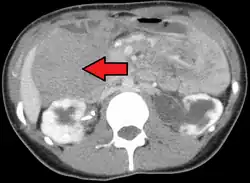

Tumor desmoide

El tumor desmoides (conocido también como fibromatosis agresiva) se trata de grandes masas infiltrantes, resultado de la proliferación de miofibroblastos bien diferenciados, que recidivan con frecuencia.[1]

Los tumores desmoides se tratan de masas mal delimitadas, firmes, de color gris-blando, con un tamaño entre 1 y 15 cm en su diámetro máximo. Son elásticas y duras, y producen una infiltración considerable del músculo, el nervio y la grasa circundantes.